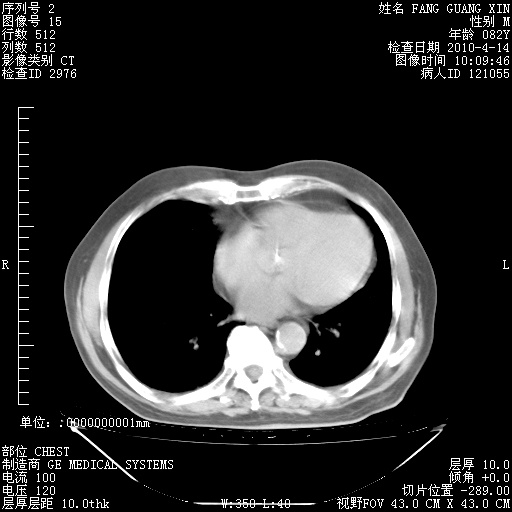

4月14日肺部CT

23.JPG

24.JPG

25.JPG

26.JPG

肺部CT平扫未见异常。